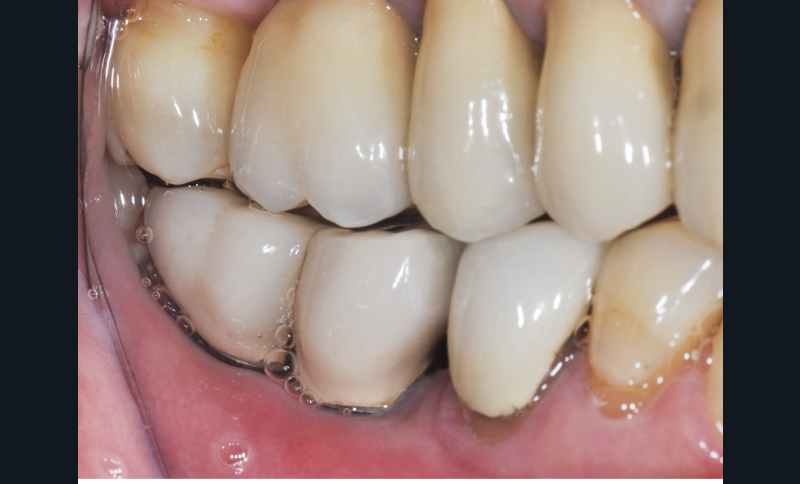

– la mucosite péri-implantaire, définie comme une inflammation réversible des tissus mous péri-implantaires sans atteinte osseuse (fig. 1a, b) ;